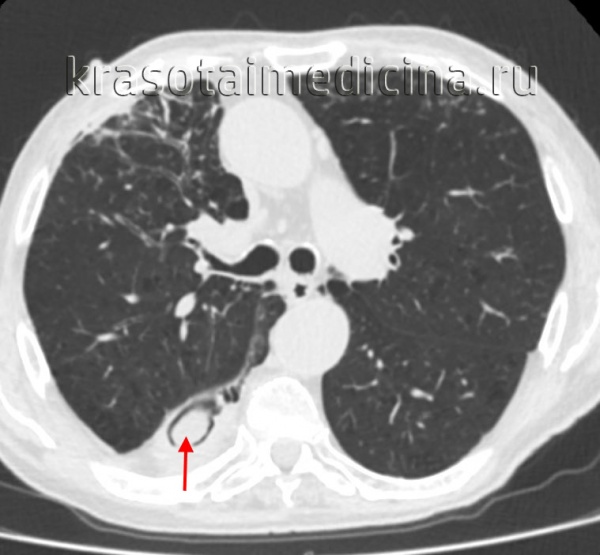

- Лучевая диагностика.Рентгенологическая картина в легких отличается разнообразием. Определяются нестойкие эозинофильные инфильтраты, плотные округлые или шаровидные тени с полостями распада, расположенные преимущественно в верхних долях лёгких, мелкоочаговая диссеминация. Характерным признаком аспергилломы является наличие серповидного просветления в полости округлого или овального образования, которое смещается при изменении положения тела (симптом погремушки). При заполнении полости аспергилломы контрастом грибные массы всплывают (симптом поплавка).

КТ ОГК. Полостное объемное образование в нижней доле правого легкого, частично заполненное грибковыми массами.